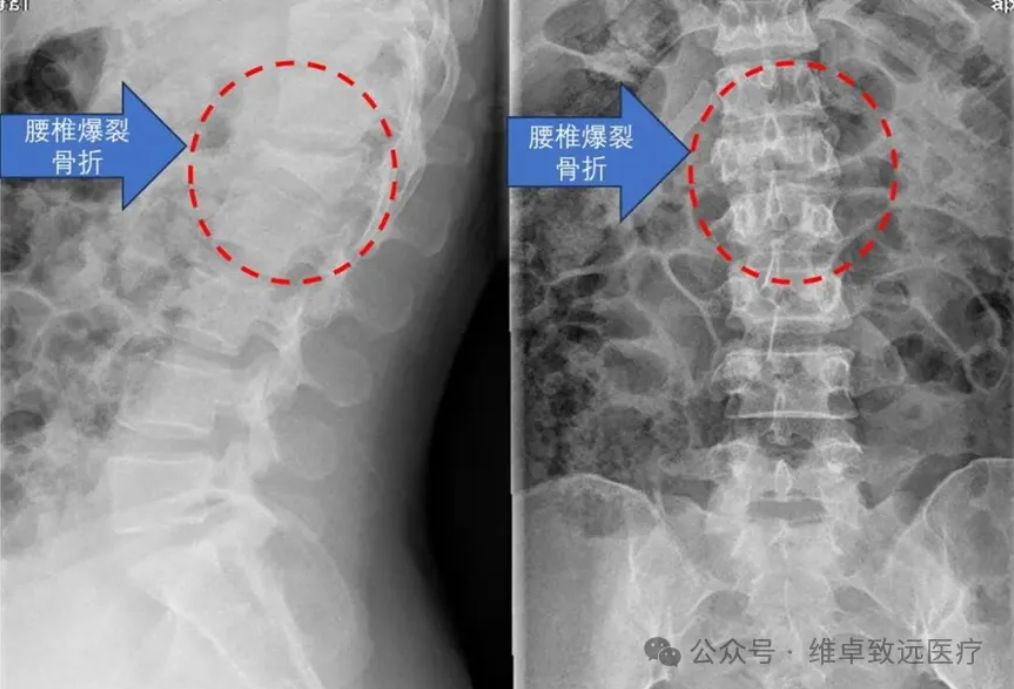

危急病情: 高坠致椎体爆裂骨折,神经受压命悬一线 术前X光:提示腰1椎体爆裂骨折 患者林女士(化名),29岁,因意外从近十米高处坠落,当即出现腰背部剧烈疼痛伴右下肢放射痛,被家人紧急送至广东医科大学附属医院脊柱外科二区就诊。 入院后,脊柱相关影像学检查结果显示:患者腰1椎体爆裂性骨折,部分碎裂骨块向后突入椎管,导致椎管明显狭窄,后方脊神经受到直接压迫。 术前 MRI: 提示有游离骨块向后移位压迫神经, 椎管容积明显变小 据主治医生介绍,该患者病情危急且复杂:不仅椎体及附件粉碎严重,存在骨折块移位刺激神经的情况,左侧椎弓根更出现断裂,传统手术中精准置入椎弓根螺钉的难度极大。若手术操作不当,可能导致永久性神经损伤、下肢瘫痪等严重后果,对手术的精准度和安全性提出了极致要求。 术前 CT: 提示腰 1 椎体爆裂骨折,右侧椎弓根断裂 (图中红色箭头所示) 技术革新: 星航导航系统,构建全流程数字化手术平台 传统脊柱内固定手术中,尤其是面对骨折粉碎、解剖结构异常的复杂病例时,椎弓根螺钉的置入往往依赖医生的临床经验和术中X光片的反复透视,如同“盲人摸象”,不仅存在置钉位置不佳的风险,还可能损伤神经血管,且术中辐射暴露较多。 为突破这一技术瓶颈,广东医科大学附属医院前瞻性引进由维卓致远创新研发的星航骨科手术导航系统。该系统由中国工程院唐佩福院士牵头,汇聚顶尖骨科专家与工程师智慧,历时四年研制而成,已斩获多项国家发明专利及创新医疗器械认证。 其核心优势并非单一导航功能,而是构建了“影像交互-手术规划-精准导航” 的全流程数字化手术平台,通过底层技术融合,系统性提升脊柱外科疑难重症的诊疗能力,彰显了我院紧跟医疗科技前沿的战略眼光。 精准手术: 手术规划 + 实时导航,实现 “所见即所得” 维卓致远导航系统手术规划 本次手术的核心技术亮点在于星航导航系统 “打破时空限制” 的精准导航能力。术前,林颢教授带领医疗团队将患者腰椎CT数据导入系统,利用其手术规划模块,在三维模型上自动识别骨折椎体,精准规划每颗螺钉的最佳植入路径、直径及长度,并从数字耗材库中预选匹配螺钉进行模拟植入,形成个性化 “数字手术蓝图”。 与传统导航需依赖昂贵笨重的术中三维扫描设备(如O型臂)重新获取影像匹配不同,星航导航采用多模态配准技术,直接将术前三维CT规划与术中普通二维X光片精准匹配,实现三维术中导航,如同为手术视野加载“GPS定位”与“实时透视”功能。医生可在导航屏幕上实时查看虚拟螺钉路径与实际解剖结构的完美叠加,真正实现“所见即所得”的精准操作。 12月9日,在充分术前准备后,手术正式启动。在星航导航系统的实时引导下,林颢教授凭借二十余年丰富的手术经验,娴熟完成导针置入、开路、螺钉固定等操作,每一步都精准避开重要神经和血管。 整个置钉过程流畅高效,不仅大幅减少术中透视次数、降低辐射暴露,更确保了内固定的最佳生物力学稳定性。术后复查显示,所有椎弓根螺钉位置精准,骨折复位满意,椎管容积有效恢复,患者神经压迫症状迅速缓解,目前恢复状况良好。 术后复查:椎弓根螺钉位置完美,骨折复位良好 专家解读: 技术赋能,开启脊柱外科精准治疗新时代 骨科中心主任、脊柱外科专家魏劲松教授表示:“对于林女士这类复杂爆裂性骨折病例,椎弓根置钉的容错率极低。星航导航系统提供的毫米级精准指引,显著提升了手术安全性与疗效可预期性。此次成功实践,不仅为我们开展更复杂的脊柱畸形矫正、微创手术积累了宝贵经验,更为科室临床技术创新与科研发展开辟了新思路。” 林颢教授强调,星航导航系统的成功应用,是骨科手术从“经验依赖”向“数据驱动、精准可视”转型的重要里程碑。其术前规划让手术方案更优化,术中多模态配准技术则破解了传统导航对昂贵设备的依赖难题,真正实现精准、微创、高效的诊疗目标,对患者、医生与医院均具有重大意义。” 左二为林颢(主刀手术中) 作为粤西地区医疗高地,广东医科大学附属医院始终勇于拥抱医疗科技前沿,持续提升诊疗服务水平。此次粤西首例星航骨科导航系统辅助脊柱手术的成功开展,是医院技术创新与学科建设的又一重要成果。 未来,医院将继续探索推广数字化智能手术技术,让更多医疗创新成果惠及广大患者,为推动骨科手术精准化、微创化、智能化发展贡献 “附院力量”。